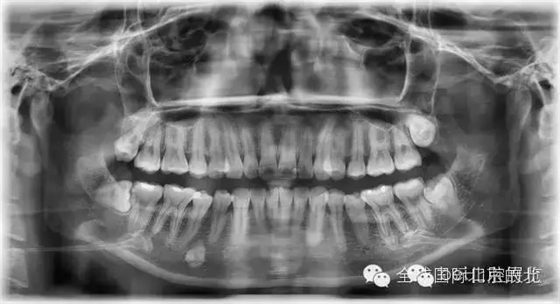

常規(guī)X-RAY全景片檢查

一個病人進來我們不單單要關(guān)注患牙,而且要關(guān)注他們?nèi)诘难例X情況,卡瓦的跨學(xué)科病例大賽讓我更加重視了患者的全局觀,雖然患者暫時不一定會處理,但是作為我們醫(yī)生有必要告訴他們,選擇權(quán)交給患者自己,也希望和所有醫(yī)生共勉。

先看看患者別的情況: